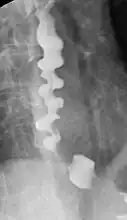

| A barium swallow showing a corkscrew appearance due to distal esophageal spasm | |

Several radiographic findings are suggestive of DES, such as a "corkscrew esophagus" or "rosary bead esophagus" appearance on barium swallow x-ray, although these findings are not unique to DES.[4]